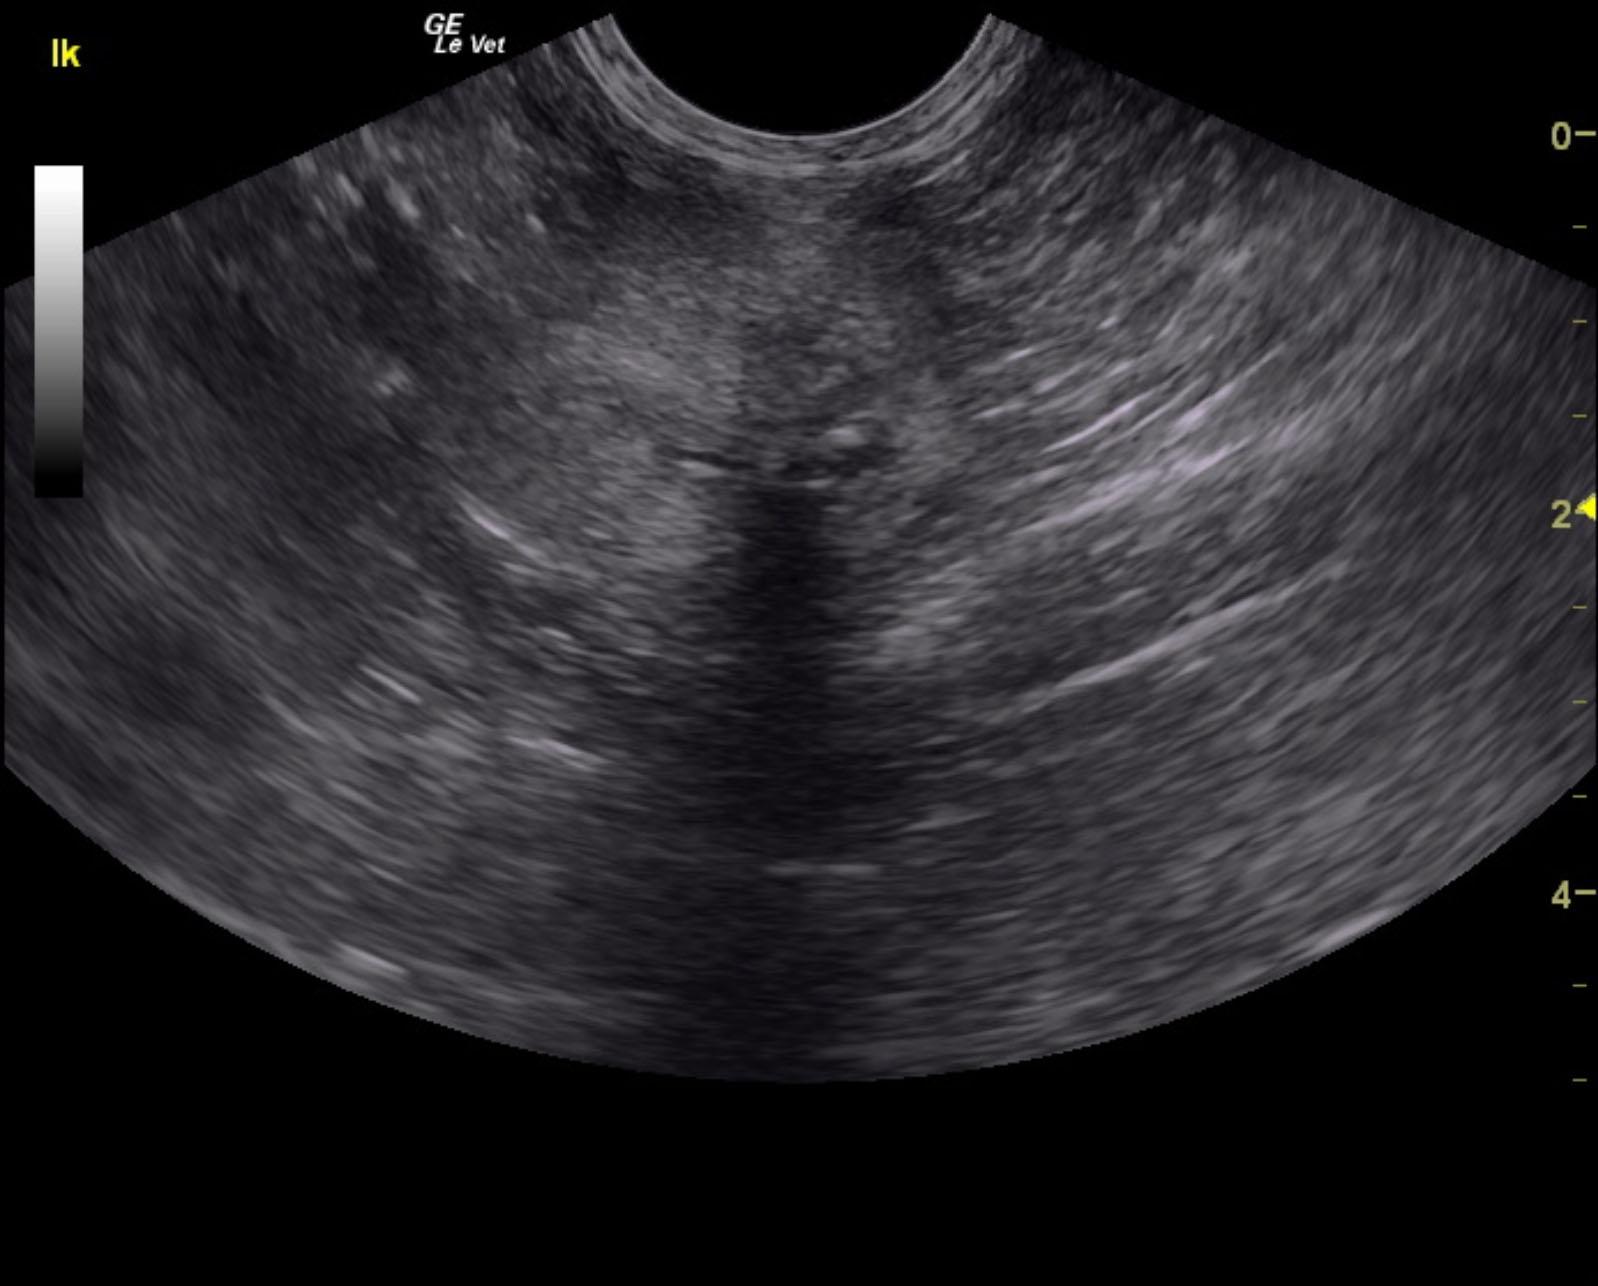

A 10-year-old neutered male Maine Coon cat with a history of lethargy and vomiting was presented for evaluation of renal failure. Cardiac murmur was present on physical examination. On urinalysis, inappropriate SG (1.014) and hematuria were evident. Blood work showed anemia, azotemia, hyperphosphatemia, and elevated liver enzyme activity. After 24 hours of fluid therapy, there was some improvement in renal values and general patient attitude.